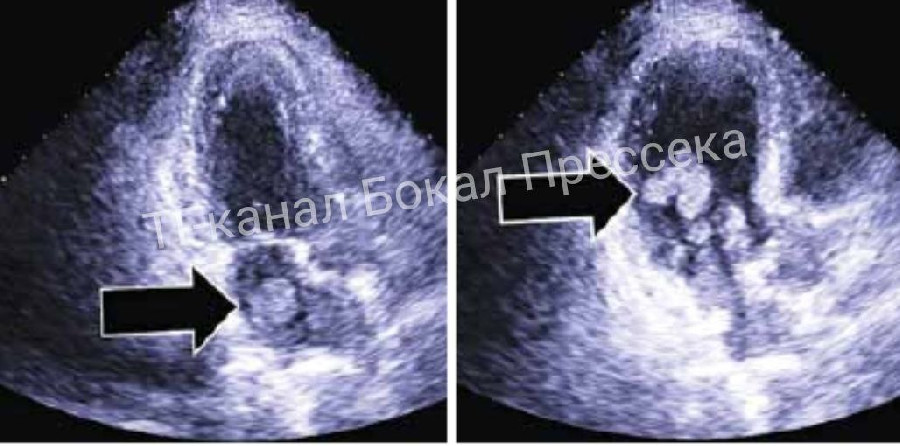

Редкая опухоль сердца спровоцировала инсульт у нижегородки. Об этом сообщает Алексей Никонов, главный редактор ИА «Стационар-пресс». Пациентку спасли врачи 13-й больницы и Нижегородского кардиоцентра. Миксома – редкая доброкачественная опухоль сердца, чаще всего поражает женщин 30-50 лет. Опухоль выявили на УЗИ сердца, консервативное лечение уже не помогало.